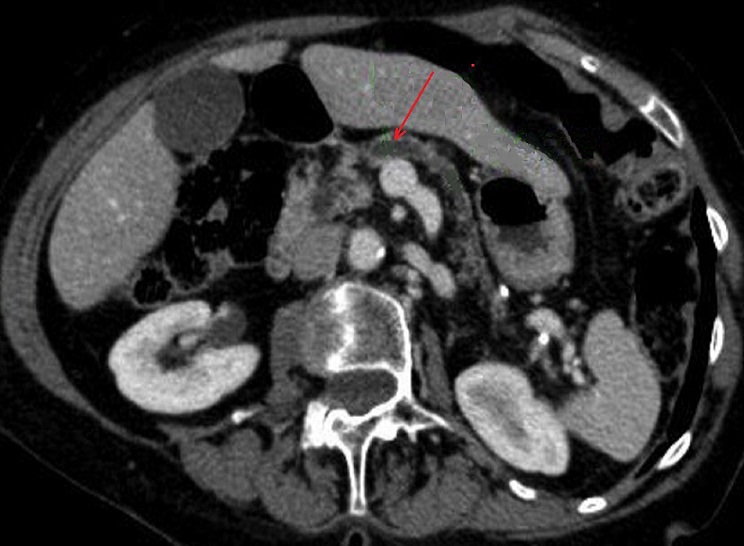

Image radiologique TDM de

evolution malignite d'une TIPMP de type canal

principale avec aspect lesionnel de dilatation ,

epaissisement et de rehaussement de sa paroi (

fleche rouge ) |